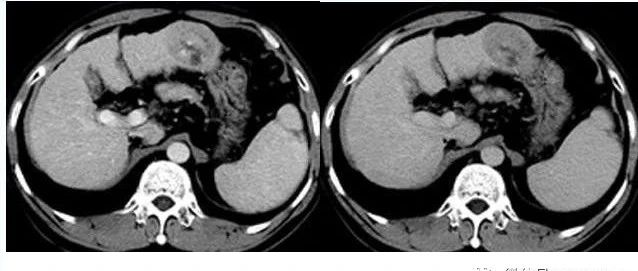

典型肝细胞肝癌一例!

欢迎下载医学影像app查看更多病例!